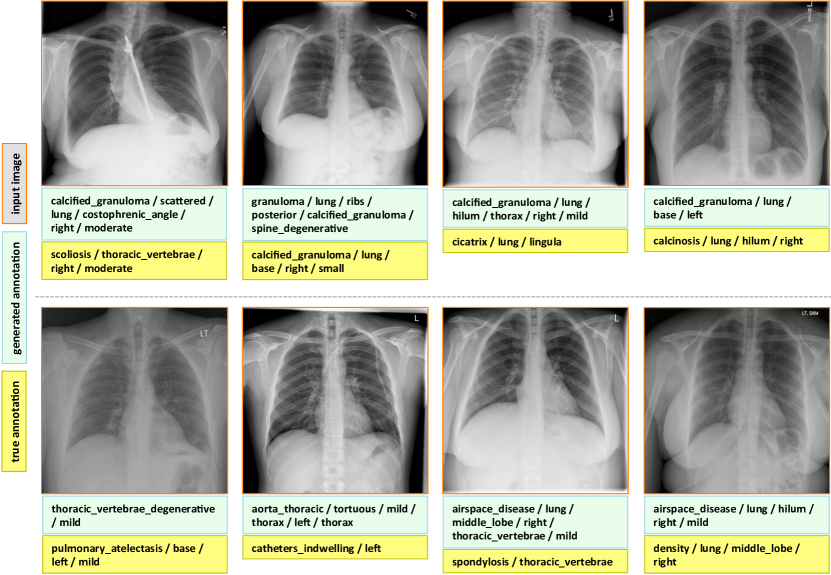

7.1 Evaluation

The final evaluated BLEU scores are provided in Table 5. We achieve better overall BLEU scores than those in Table 4 before using the joint image/text context. It is noticeable that higher BLEU-N () scores are achieved compared to Table 4, indicating that more comprehensive image contexts are taken into account for the CNN/RNN training. Also, slightly better BLEU scores are obtained using GRU on average and higher BLEU-1 scores are acquired using LSTM, although the comparison is empirical. Examples of generated annotations on the chest x-ray images are shown in Figure 6. These are generated using the GRU model, and more examples can be found in the supplementary material.

Appendix C More Annotation Generation Examples

More annotation generation examples are provided in Figures 10 and 11. Overall, the system generates promising results on predicting disease (labels) and its context (attributes) in the images. However, rare disease cases are more difficult to detect. For example, the cases pulmonary_atelectasis, spondylosis, and density (Figure 10), as well as foreign_bodies, atherosclerosis, costophrenic_angle, deformity (Figure 11) are much rarer in the data than calcified_granuloma, cardiomegaly, and all the frequent cases listed in Table 1 of the main paper.

Furthermore, the (left or right) location of the disease cannot be identified in a lateral view (obtained by scanning the patient from the side), as shown in Figure 11. Since our dataset contains a limited number of disease cases, we treat each x-ray image and report as a sample, and do not account for different views.

For future work, we plan to improve prediction accuracy by both (a) accounting for the different views, and (b) collecting a larger dataset to better account for rare diseases.